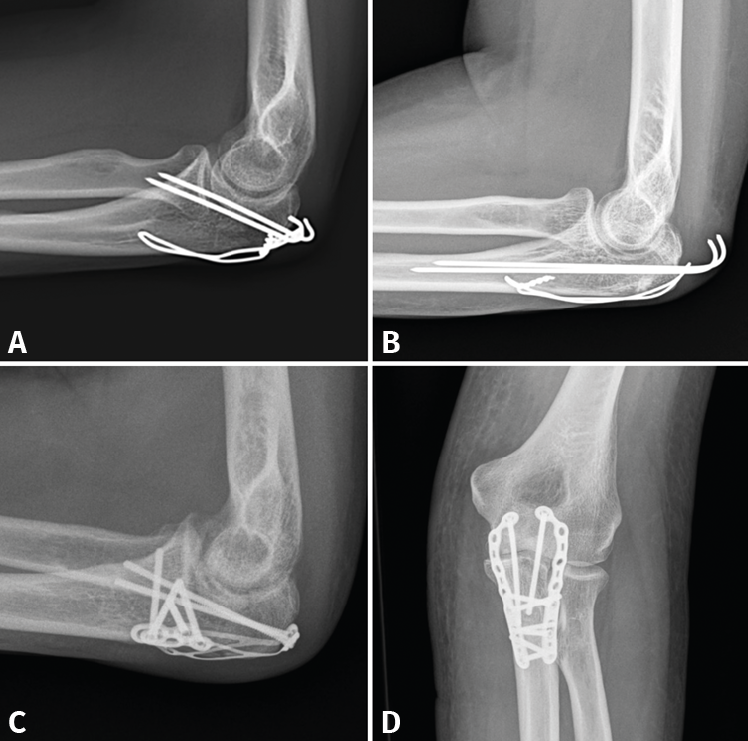

- 2A/2B: son las más frecuentes. La técnica de elección en las fracturas simples en 2 partes es un cerclaje de alambre (obenque) sobre 2 agujas de Kirschner (AK) ancladas a la cortical anterior o colocadas intramedulares. En el primer caso, tenemos riesgo de lesionar las estructuras neurovasculares volares, por lo que no deben sobresalir más de 10 mm; en el segundo caso, el riesgo de que migren proximalmente es mayor(34,35). Se pensó que con este montaje las fuerzas de tensión se transforman en fuerzas de compresión, pero varios estudios realizados no han podido demostrar este principio(36). En las conminutas 2B se recomienda fijación con placa, precisamente para evitar la excesiva comprensión de la cavidad sigmoidea que llevaría a una artrosis precoz. Se recomiendan las placas premoldeadas LCP (locking compression plate). Su efectividad y seguridad están de sobra probadas; sin embargo, al ir en una posición dorsal y ser el cúbito subcutáneo, pueden producir irritación de los tejidos blandos y con cierta frecuencia hay que retirarlas. Aun así, el índice de retirada es mucho mayor en los cerclajes, que puede llegar hasta el 90%(37,38). La alternativa es usar 2 placas laterales de bajo perfil colocadas a ambos lados de la cresta, una medial y otra lateral, que además tienen la ventaja de permitir una fijación bicortical de los fragmentos más proximales. En cualquier caso, los estudios demuestran que ambos métodos tienen buenos resultados y no existen diferencias a corto plazo. Últimamente, se están publicando modificaciones a la técnica clásica del obenque, usando una sutura trenzada de alta resistencia en lugar de alambre(39). En este caso solo tendríamos que retirar las AK y este es un proceso mucho menos invasivo (Figura 8).

Figura 8. Ejemplos de fracturas de olécranon en 2 partes (tipo 2A) fijadas con obenque (A y B) y fracturas de tipo 2B fijadas con distintos diseños de placas (C y D).